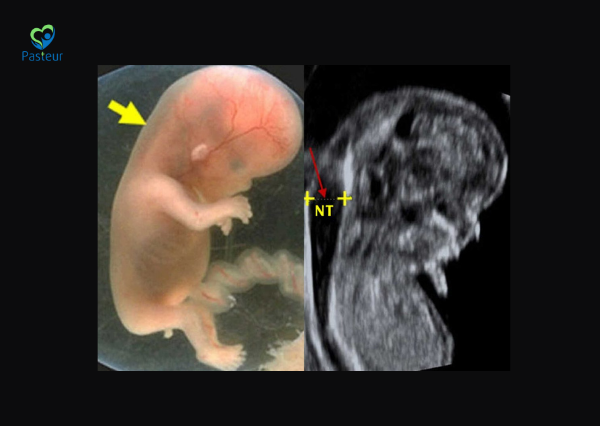

Độ mờ da gáy (Nuchal Translucency – NT) là khoảng dịch nằm dưới lớp da ở vùng sau cổ của thai nhi, có thể quan sát được thông qua siêu âm trong 3 tháng đầu thai kỳ.

Độ mờ da gáy tăng có nguy hiểm không? Chỉ số bình thường theo tuần thai Ảnh minh họa

Theo khuyến cáo của American College of Obstetricians and Gynecologists, độ mờ da gáy nên được đo khi thai từ 11 tuần đến 13 tuần 6 ngày, khi chiều dài đầu mông của thai nằm trong khoảng 45–84 mm.